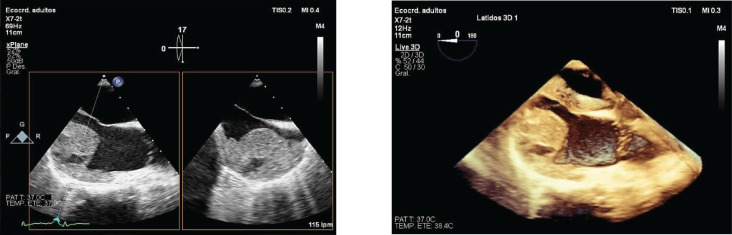

原发性心脏血管肉瘤是一种非常罕见且生长迅速的肿瘤,其中妊娠与原发性心脏血管肉瘤同时发生极为罕见。这使得诊断变得困难,有时甚至很晚,导致从发现的那一刻起预后就很差。我们提出的情况下,38岁的孕妇在妊娠第16周诊断为产科抗磷脂综合征谁来到急诊室虚弱,呼吸困难,心动过速和低血压。经胸超声诊断为心包填塞。她因外源性心源性休克住进重症监护室。经食管超声检查显示右心房有一个大的杂色肿块,提高了心房血栓和心肌肿瘤的鉴别诊断。择期剖宫产于妊娠22周。几个月后,患者因非常不利的临床进展再次入院,经历弥漫性肺泡出血/血管炎,生命支持措施难治性。同意在等待心脏内活检的解剖病理报告时限制治疗努力,随后确认心脏血管肉瘤的组织学性质。本病例报告强调其罕见性,表现出非特异性的临床表现,这使我们认为右心房血栓形成和血管肉瘤的致命预后,主要与由于诊断较晚导致疾病进展有关。

Primary cardiac angiosarcoma is a very rare and fast-growing tumour, where the coincidence of pregnancy and primary cardiac angiosarcoma is extremely rare. This makes diagnosis difficult and sometimes late, resulting in a poor prognosis from the moment of detection. We present the case of a 38-year-old pregnant woman in the 16th week of gestation diagnosed with obstetric antiphospholipid syndrome who came to the emergency department with asthenia, dyspnea, tachycardia and hypotension. A transthoracic ultrasound was performed with a diagnosis of pericardial tamponade. She was admitted to the intensive care unit for extrinsic cardiogenic shock. Transesophageal echography was performed, showing a large variegated mass in the right atrium, raising the differential diagnosis between atrial thrombus and myocardial tumour. Elective cesarean section was performed at 22 weeks of gestation. Months later, the patient was readmitted with a very unfavorable clinical evolution, experiencing diffuse alveolar hemorrhage/vasculitis refractory to life support measures. It was agreed to limit the therapeutic effort while awaiting the anatomopathological report of intracardiac biposia, subsequently confirming the histological nature of cardiac angiosarcoma. This case report highlights its rarity, showing a non-specific clinical presentation, which directed us towards a thrombosis in the right atrium and the fatal prognosis of angiosarcoma, mainly related to the progression of the disease due to a late diagnosis.